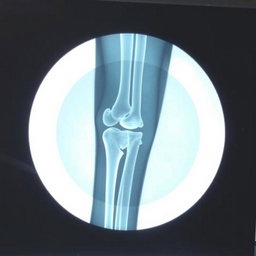

"Make medical report for leg fracture of patient, heading hospital name " national medical college hospital" hospital address: birgunj with given patient details name "Prabesh Kumar Sah" Age "18" and sex "male""